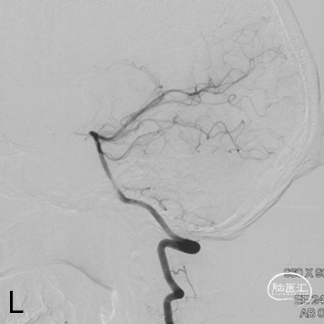

术前造影

双侧颈内动脉正侧位造影见前颅窝底硬脑膜动静脉瘘,双侧筛前动脉、筛后动脉向瘘口供血,通过皮层静脉向上矢状窦引流。

双侧颈外动脉正侧位造影见镰前动脉向瘘口供血。

左侧椎动脉正侧位造影未见明显异常。